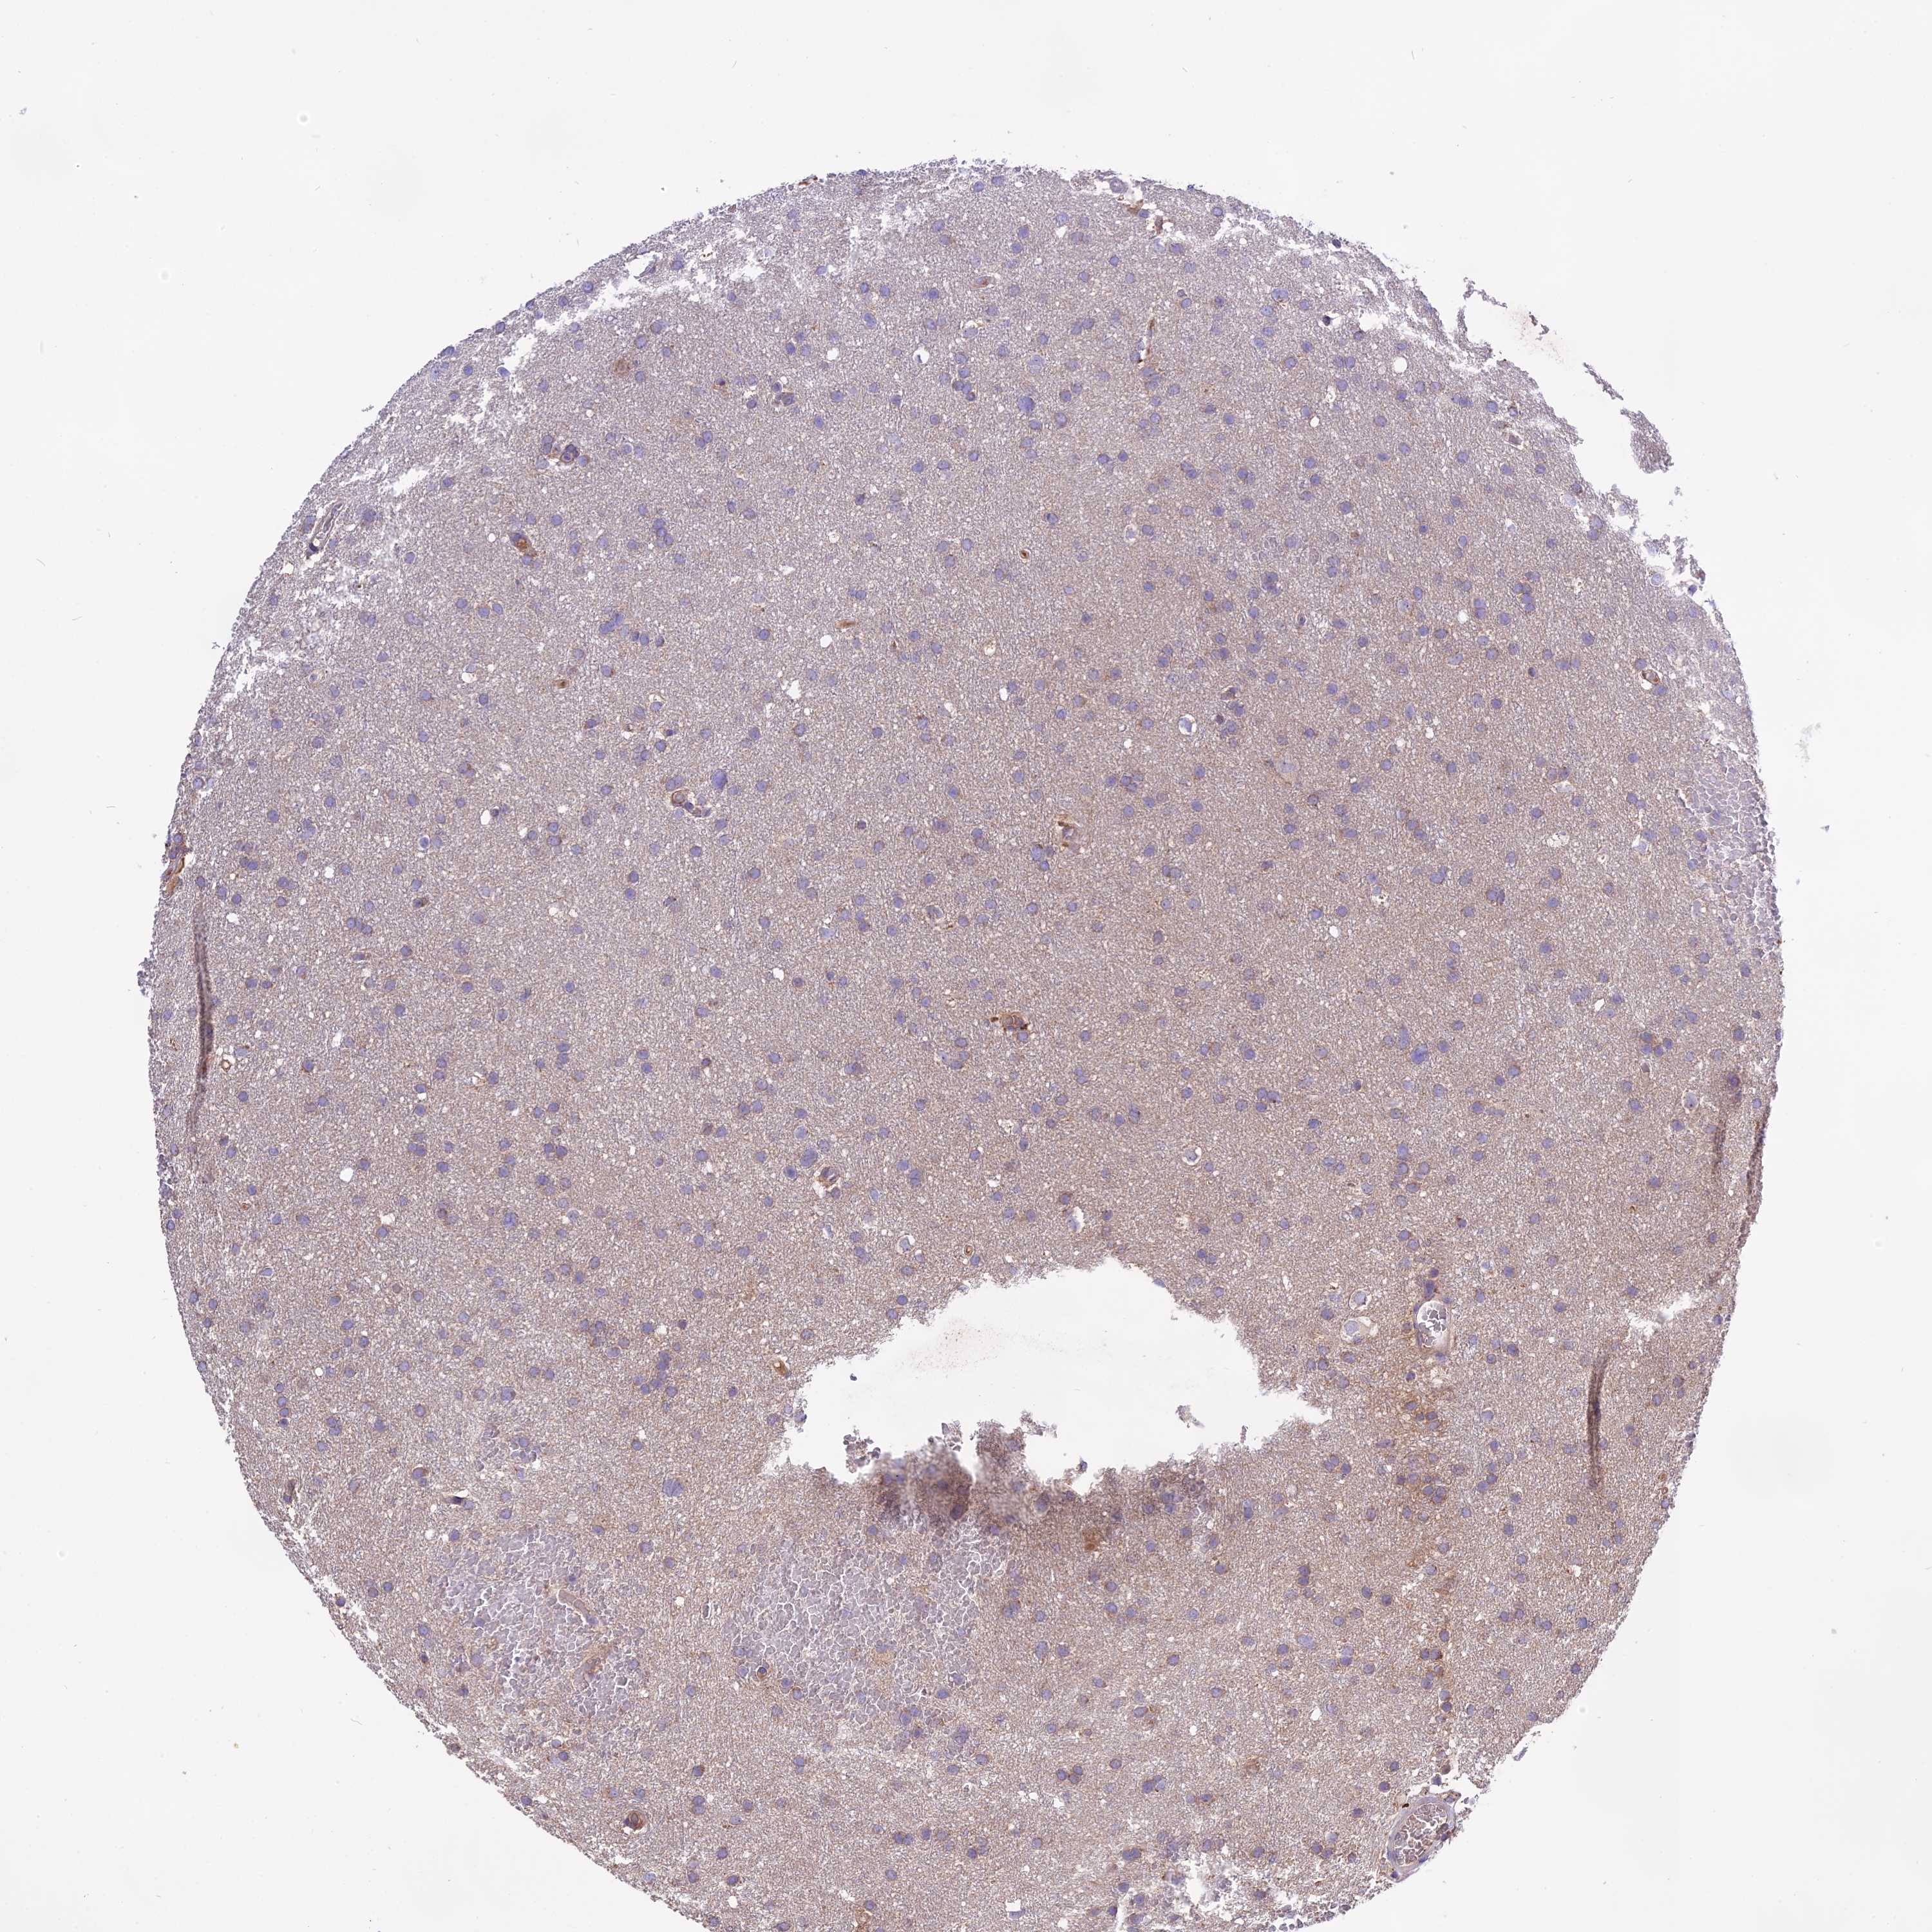

GLIOMA - Protein expressioni

A mouse-over function shows sample information and annotation data. Click on an image to view it in a full screen mode. Samples can be filtered based on level of antibody staining by selecting one or several of the following categories: high, medium, low and not detected. The assay and annotation is described here.

Note that samples used for immunohistochemistry by the Human Protein Atlas do not correspond to samples in the TCGA dataset.

Antibody stainingi

Antibody staining in the annotated cell types in the current human tissue is reported as not detected, low, medium, or high, based on conventional immunohistochemistry profiling in selected tissues. This score is based on the combination of the staining intensity and fraction of stained cells.

Each image is clickable and will lead to virtual microscopy that enables deeper exploration of all samples and also displays staining intensity scores, fraction scores and subcellular localization as well as patient and tissue information for each sample.

Antibody HPA041252

Antibody HPA041466

Glioma, malignant, High grade

Glioma, malignant, Low grade